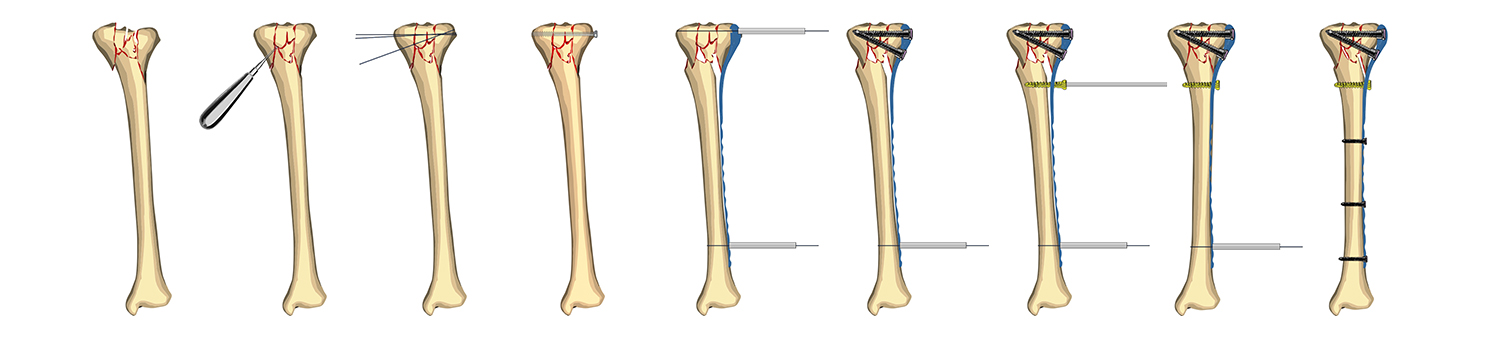

En la entrada dedicada a los clavos intramedulares decíamos que una de sus limitaciones es que no controlan bien las fracturas articulares. Si bien es posible utilizar las placas en muchas otras indicaciones (correcciones angulares, pseudoartrosis, artrodesis, etc.), posiblemente su principal indicación a día de hoy es el tratamiento de las fracturas con afectación articular.

Del mismo modo, parece que en fracturas diafisarias simples en huesos largos (fémur, tibia, húmero…), el uso de clavos intramedulares podría estar más recomendado.